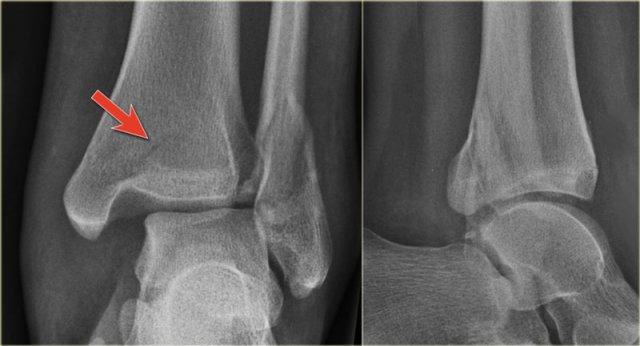

Các hình ảnh cho thấy một trường hợp gãy Weber B rõ ràng.

Trên tư thế thẳng (AP), đường thấu quang dạng tuyến tính là dấu hiệu gợi ý gãy tertius (mũi tên đỏ).

Dấu hiệu này xuất hiện do sự lệch trục nhẹ của mảnh gãy.

Tương tự, trong một số trường hợp, sự lệch trục có thể tạo ra một đường tăng tỷ trọng dạng tuyến tính.

Trong trường hợp này, có gãy Weber B kèm theo bong điểm bám mắt cá trong.

Đường tăng tỷ trọng trên tư thế thẳng (AP) gợi ý một mảnh gãy tertius lớn.

Gãy tertius này cũng có thể thấy trên tư thế nghiêng, nhưng trong nhiều trường hợp chúng ta cần kết hợp thông tin từ cả hai tư thế nghiêng và thẳng để chẩn đoán gãy tertius.